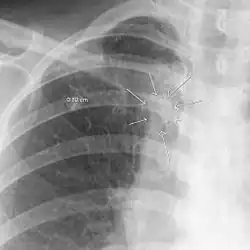

Im Röntgenbild und CT kann sich die pulmonäre Aspergillosis als ein air crescent sign manifestieren (Halbmond-Zeichen).[3] Das Gesamt-IgE ist in der Regel erhöht, es lässt sich meist ein spezifisches Aspergillus IgE sowie spezifisches IgG nachweisen.[4] Der Labornachweis der rekombinanten Aspergillen-Allergene rAspf4 sowie rAspf6 ist hochspezifisch für die ABPA.